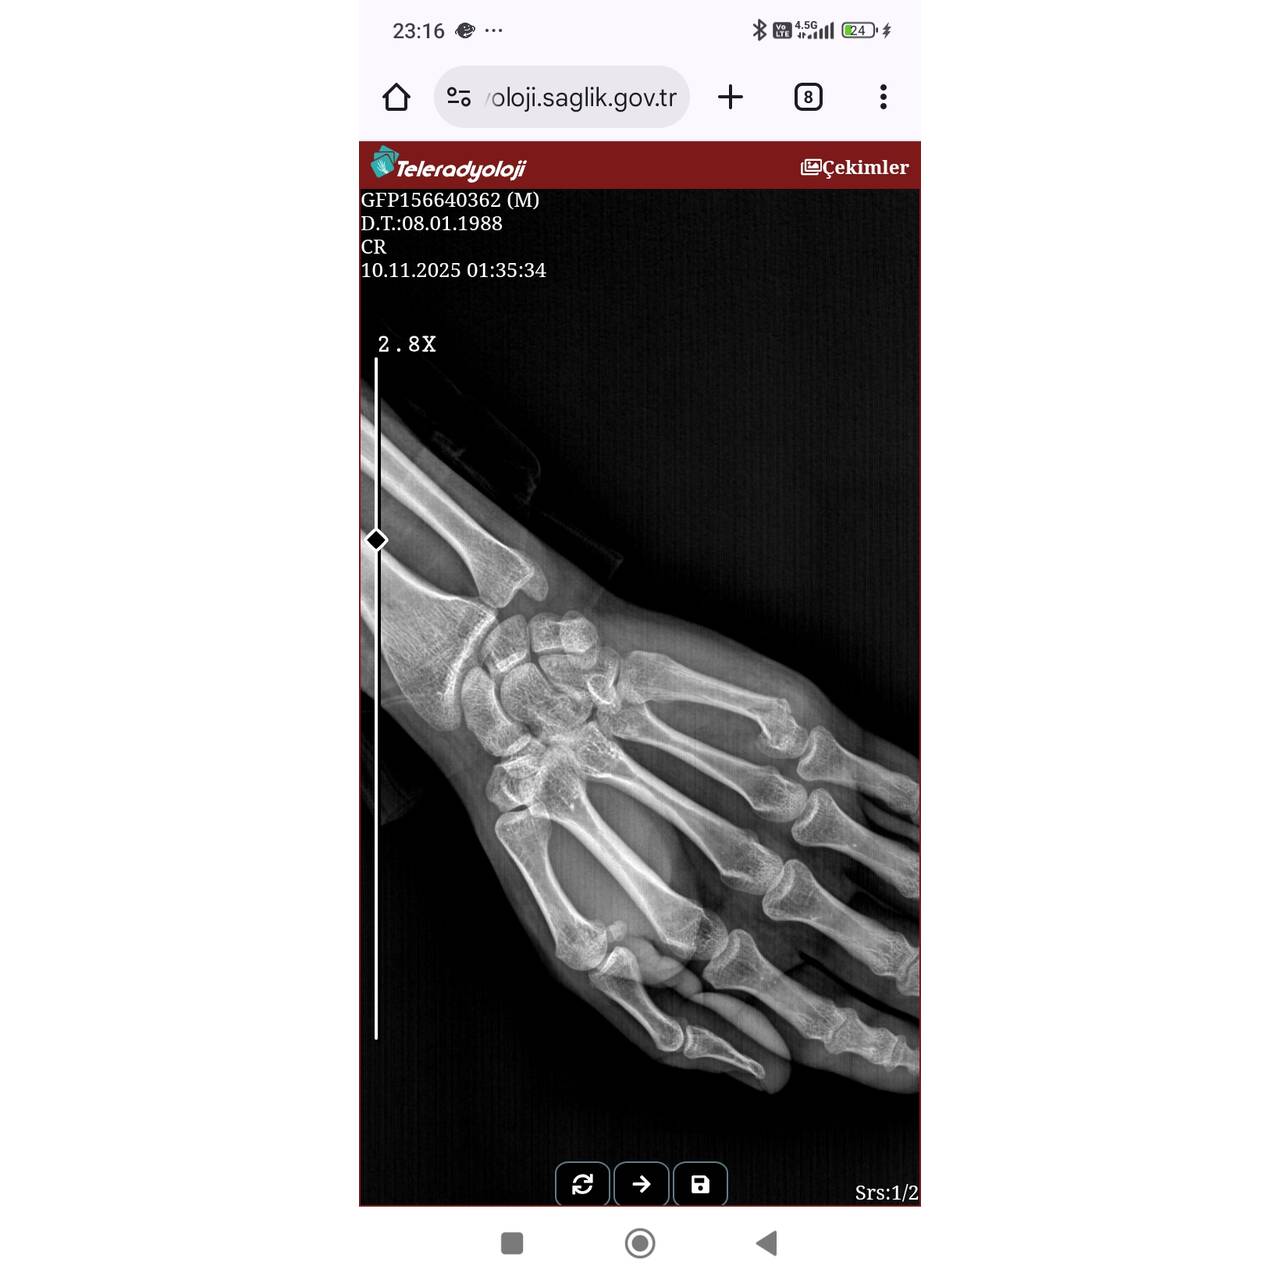

Elimde boksör kırığı diye tabir edilen bir kırık meydana gelmişti ve bu doktor ilgilendi çok içime sinmedi ve 2 ay sonrasında bile ağrı olduğu için başka doçent doktora gittim kemiğin tam düz olmadığını ancak bu kadar bir yamukluk için de tekrar kırmaya gerek olmadığını söyledi umarım büyük kemiklerde daha titiz davranıyordur. İlk hali ve son hali görsellerdeki gibi